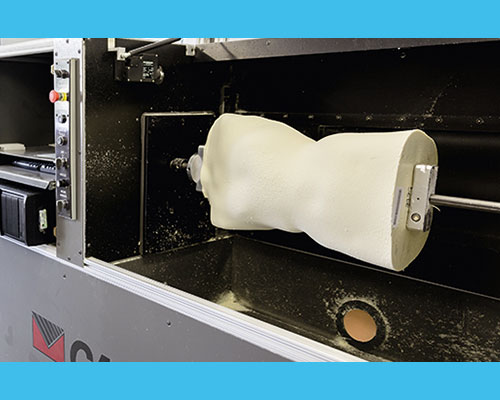

Positif (moulage) :

le moule positif est la reproduction originale du tronc du patient en 3D. Le positif sert pour le thermoformage de l’orthèse.